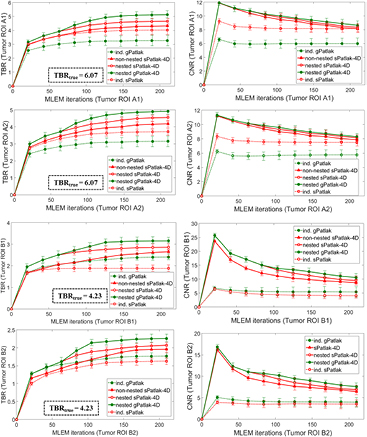

Standard image High-resolution imageFor the evaluation of the 4D simulated data, ground truth kinetic parameters were known. Thus, the quantitative analysis was first conducted in terms of percentage (%) normalized bias (NBias × 100) and normalized standard deviation or noise (NSD × 100), where NBias and NSD were calculated over  simulated realizations, according to Karakatsanis et al (2013a), paragraph 4.2. Both metrics were extracted from four characteristic tumor regions (A1, A2, B1 and B2), as a function of the number of ML-EM iterations and plotted together to form noise-bias trade-off curves for each ROI and evaluated method. In addition, we assessed the mean target to background (TBR) and contrast to noise ratio (CNR) metrics for the same tumor regions after averaging over the 20 realizations, according to equations (18) and (19) below.

In noise-free conditions, indirect and direct methods are expected to match in performance, after convergence is attained. Indeed, no visually distinct difference was observed in the noise-free Ki images between the two method classes (figure 5(a)). In the presence of noise, however, the benefit in noise and resolution of properly initialized direct 4D versus indirect Patlak analysis is illustrated when visually comparing the noisy Ki simulated images (figures 4 and 5(b)), especially for the tumor lesions of B group in the right lung. Moreover, the noise-bias trade-off curves (figure 5(c)) clearly demonstrated, for all evaluated ROIs, the superiority of 4D sPatlak and properly initialized 4D gPatlak algorithms, relative to the respective indirect methods. In particular, we observed significantly reduced noise at matched bias (resolution) and vice versa for the direct 4D versus the indirect methods in all ROIs. Finally, the 4D methods converged to distinctly smaller bias values than indirect methods, thus suggesting reduced noise-induced bias compared to indirect Patlak.

These observations were further supported by the TBR and CNR quantitative analysis on the same four Ki image ROIs in figure 6. Nevertheless, it should be noted that 4D imaging methods were associated with a relatively higher gain in CNR rather than TBR scores, as the main benefit of direct over indirect parametric reconstruction is the reduction of the noise in the Ki images. The TBR relative enhancements of 4D over indirect algorithms can be attributed to the reduction of noise-induced bias for the former, as also indicated by the noise-bias trade-off analysis in figure 5(c). Nevertheless, the ground true TBR Ki contrast, as calculated from the true input values of our simulation study, was underestimated in all cases. In all cases, the observed bias in the lesion Ki estimates and respective underestimated TBR scores becomes higher for smaller diameters (A2 and B2 ROIs), which we attribute to the partial volume effects.

Figure 6. TBR (1st column) and CNR (2nd column) quantitative analysis for A1, A2, B1 and B2 target ROIs on simulated Ki parametric images for a range of indirect and direct (s/g)Patlak methods. The same number of nested Patlak ML-EM sub-iterations and gPatlak-4D initialization scheme are employed, as for figure 5. TBR and CNR scores were averaged over 20 noise realizations with the standard deviation illustrated with error bars.

A visual inspection of the ground truth Ki and kloss images and their comparison with the noise-free reconstructed Ki images in figure 5(a) (2nd row) suggests that, in general, the gPatlak indirect 3D and direct 4D methods were associated with more accurate Ki estimates than respective sPatlak methods. Furthermore, both noise-free and noisy gPatlak 4D reconstructions yielded relatively higher Ki TBR contrast scores, than respective sPatlak reconstruction, for tumor ROIs of group B, where a relatively higher degree of uptake reversibility (k4 = 0.012) was introduced in our simulations (table 1). Thus, our observations demonstrated the theoretical advantage of gPatlak over sPatlak algorithms, when evaluating regions exhibiting non-negligible uptake reversibility. However, the same results indicated lower Ki image noise for sPatlak versus the gPatlak 4 D methods. The respective noise-bias curves (figure 5(c)) confirmed the previous findings, as they revealed smaller bias at matched noise levels and higher noise at matched resolution (bias) for gPatlak 4D reconstruction methods.

Furthermore, in terms of lesion detectability performance, the results in figure 6 suggest that the main differences between sPatlak and gPatlak 4D methods were observed in TBR and CNR scores, with TBR being affected more profoundly. We attribute this finding to the relatively higher noise levels for gPatlak imaging, even within the 4D framework. Although bias and TBR contrast are enhanced with gPatlak 4D methods, the increased noise associated with gPatlak non-linear model eventually limits gPatlak 4D CNR scores. As a result, gPatlak 4D is not increasing the CNR scores as much as it enhances the TBR scores.

3.1.4. Conventional versus nested Patlak 4D ML-EM and number of nested sub-iterations.

The expected gain in ML-EM convergence rate for the nested relative to the conventional, i.e. non-nested, 4D sPatlak implementations was illustrated qualitatively and quantitatively in figures 5(b) and (c) respectively. In particular, visual inspection of B1 and B2 lesions contrast as a function of the iteration cycles in simulated Ki images of figure 5(b) suggested a faster contrast recovery, and thus convergence rate, for the nested sPatlak Ki images. In addition, the respective noise-bias curves in figure 5(c) indicated smaller bias values at matched noise levels for the nested sPatlak 4D implementation.

Moreover, a mildly faster 4D ML-EM convergence was recorded as the number of nested sub-iterations increased per global iteration step. This is conjectured from all three plots of the 2nd column of figure 7. However, the gain in bias and TBR contrast became progressively negligible when more than 20 sub-iterations were involved, as convergence had already been established at earlier iterations in these cases. Meanwhile, the noise was being steadily deteriorated in the same cases, due to the higher number of nested updates involved per global iteration step. As a result, for higher than 20 nested sub-iterations, image noise kept increasing relatively faster than TBR lesion contrast and, consequently, CNR started dropping at later iterations. Although not included in the results, it should be noted that a very small number of sub-iterations (<10) resulted in consistently slower convergence in all nested 4D algorithms.